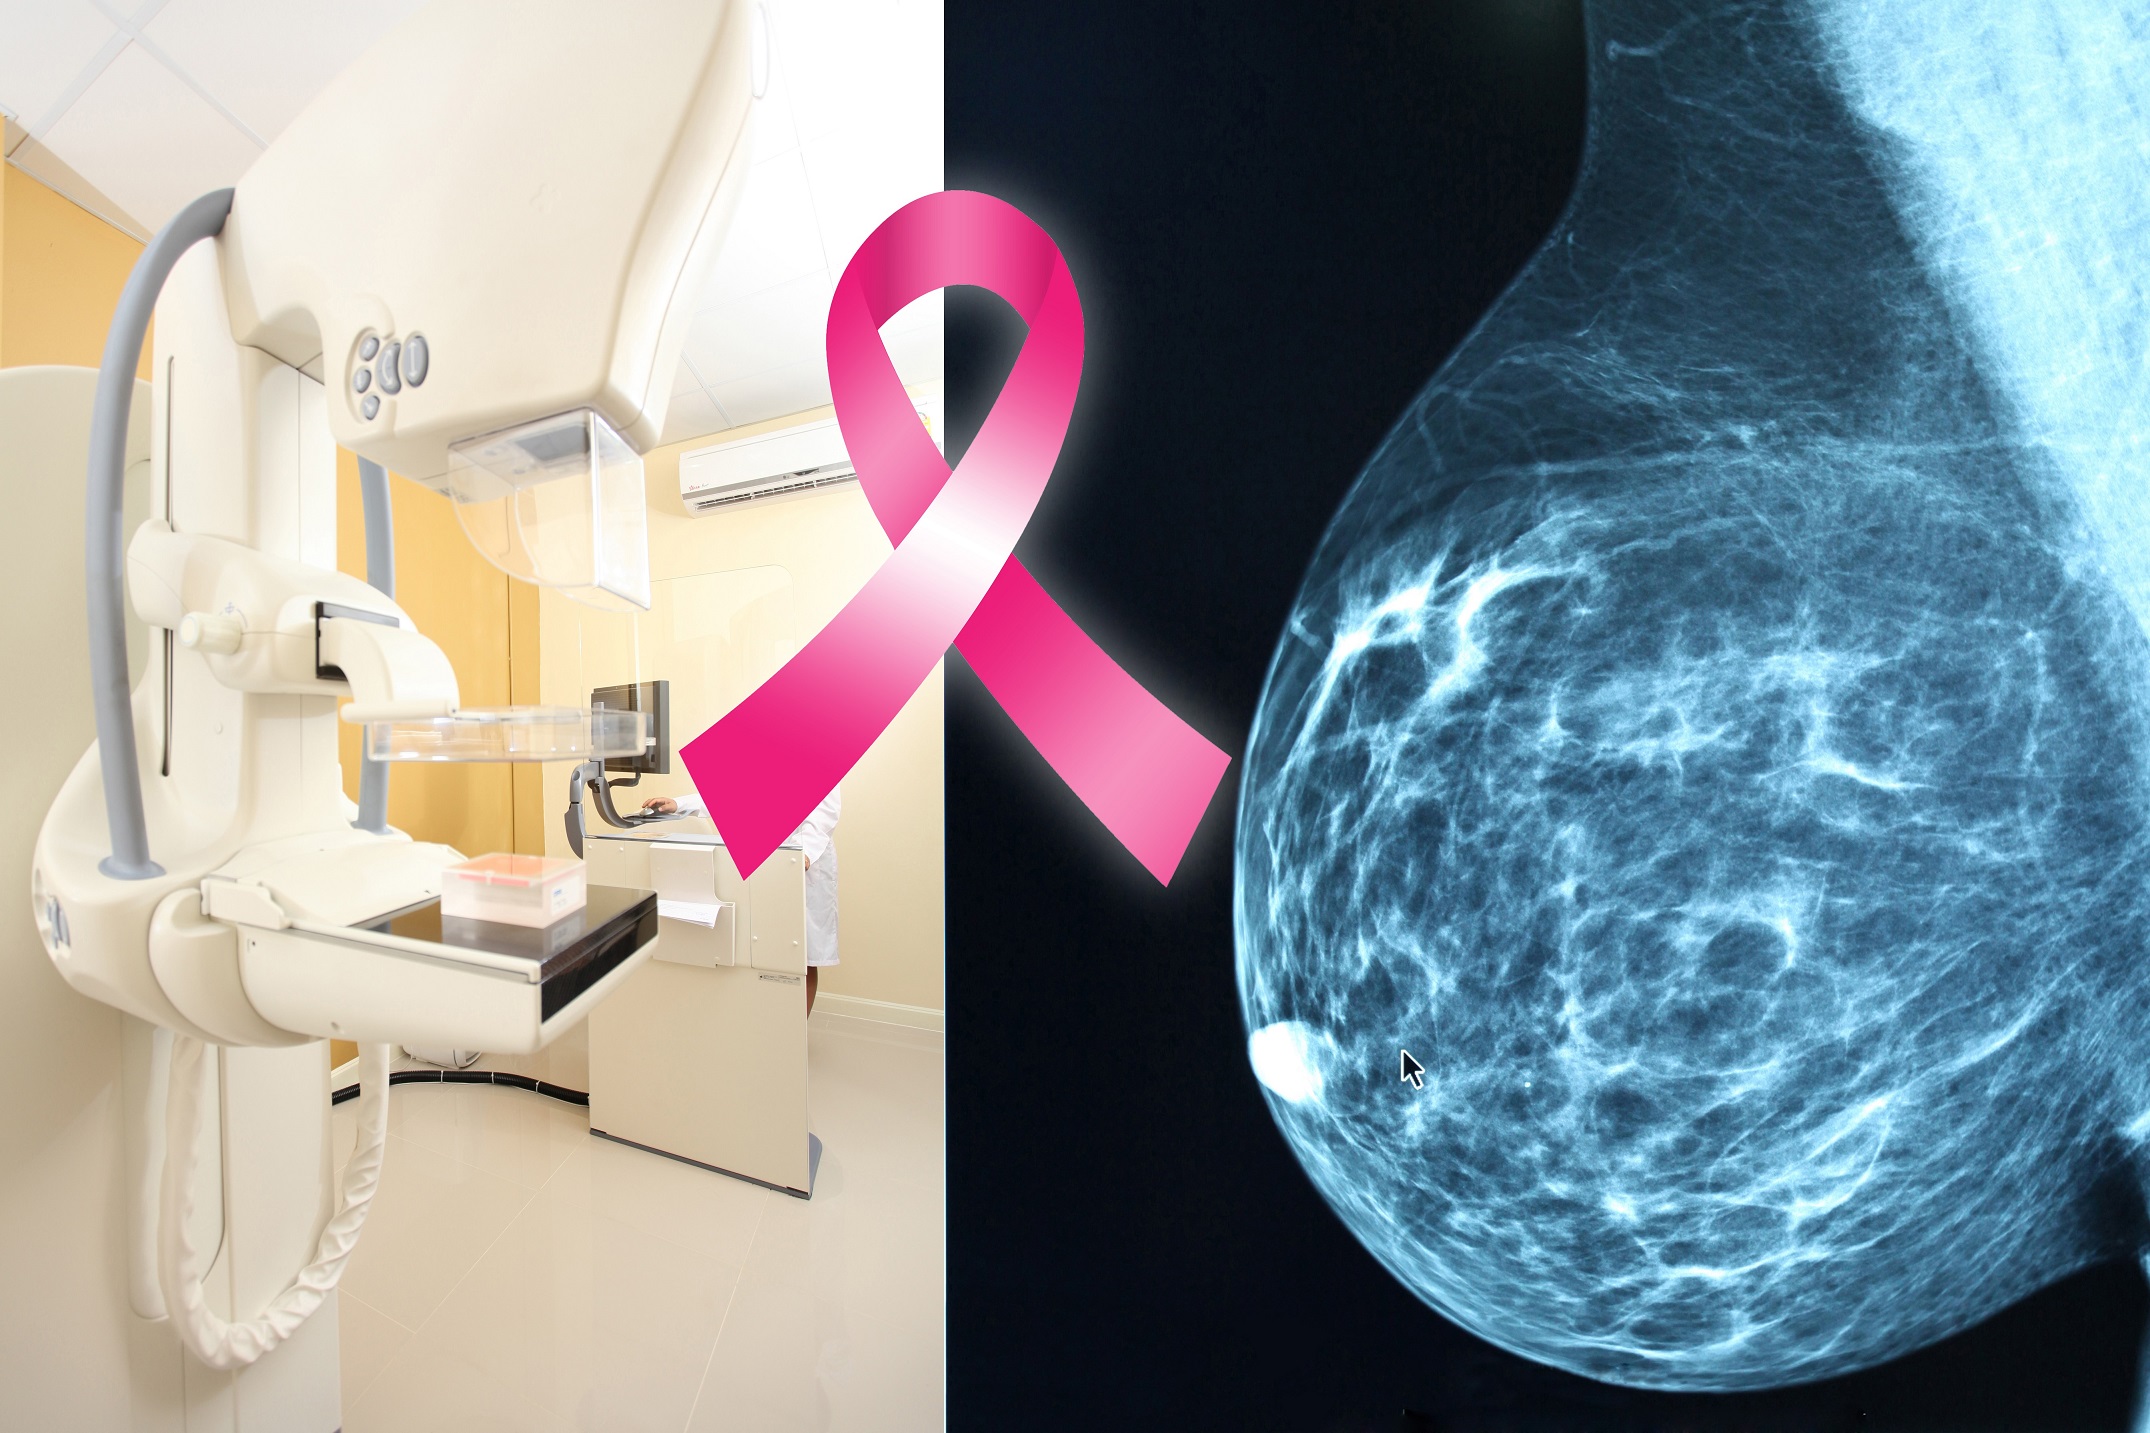

A mammogram is a radiographic image that gives a picture of the internal structure of the breast. There are two types of mammography: screening and diagnostic.

A screening mammogram is performed on women who have no evidence of breast disease. Using a mammography machine, a radiologic technologist obtains two views of each breast. Screening mammography is the best way to detect breast cancer early. A screening mammogram is similar to other screening exams such as a PAP smear, PSA for prostate cancer, fecal occult blood to detect colon cancer and a glucose test to detect diabetes.

Diagnostic mammography is performed when a possible abnormality, such as a lump, has been found on a screening mammogram or upon clinical examination of the breast. It includes special views in order to better evaluate the abnormality. A diagnostic mammogram is read by the radiologist at the time of the exam.